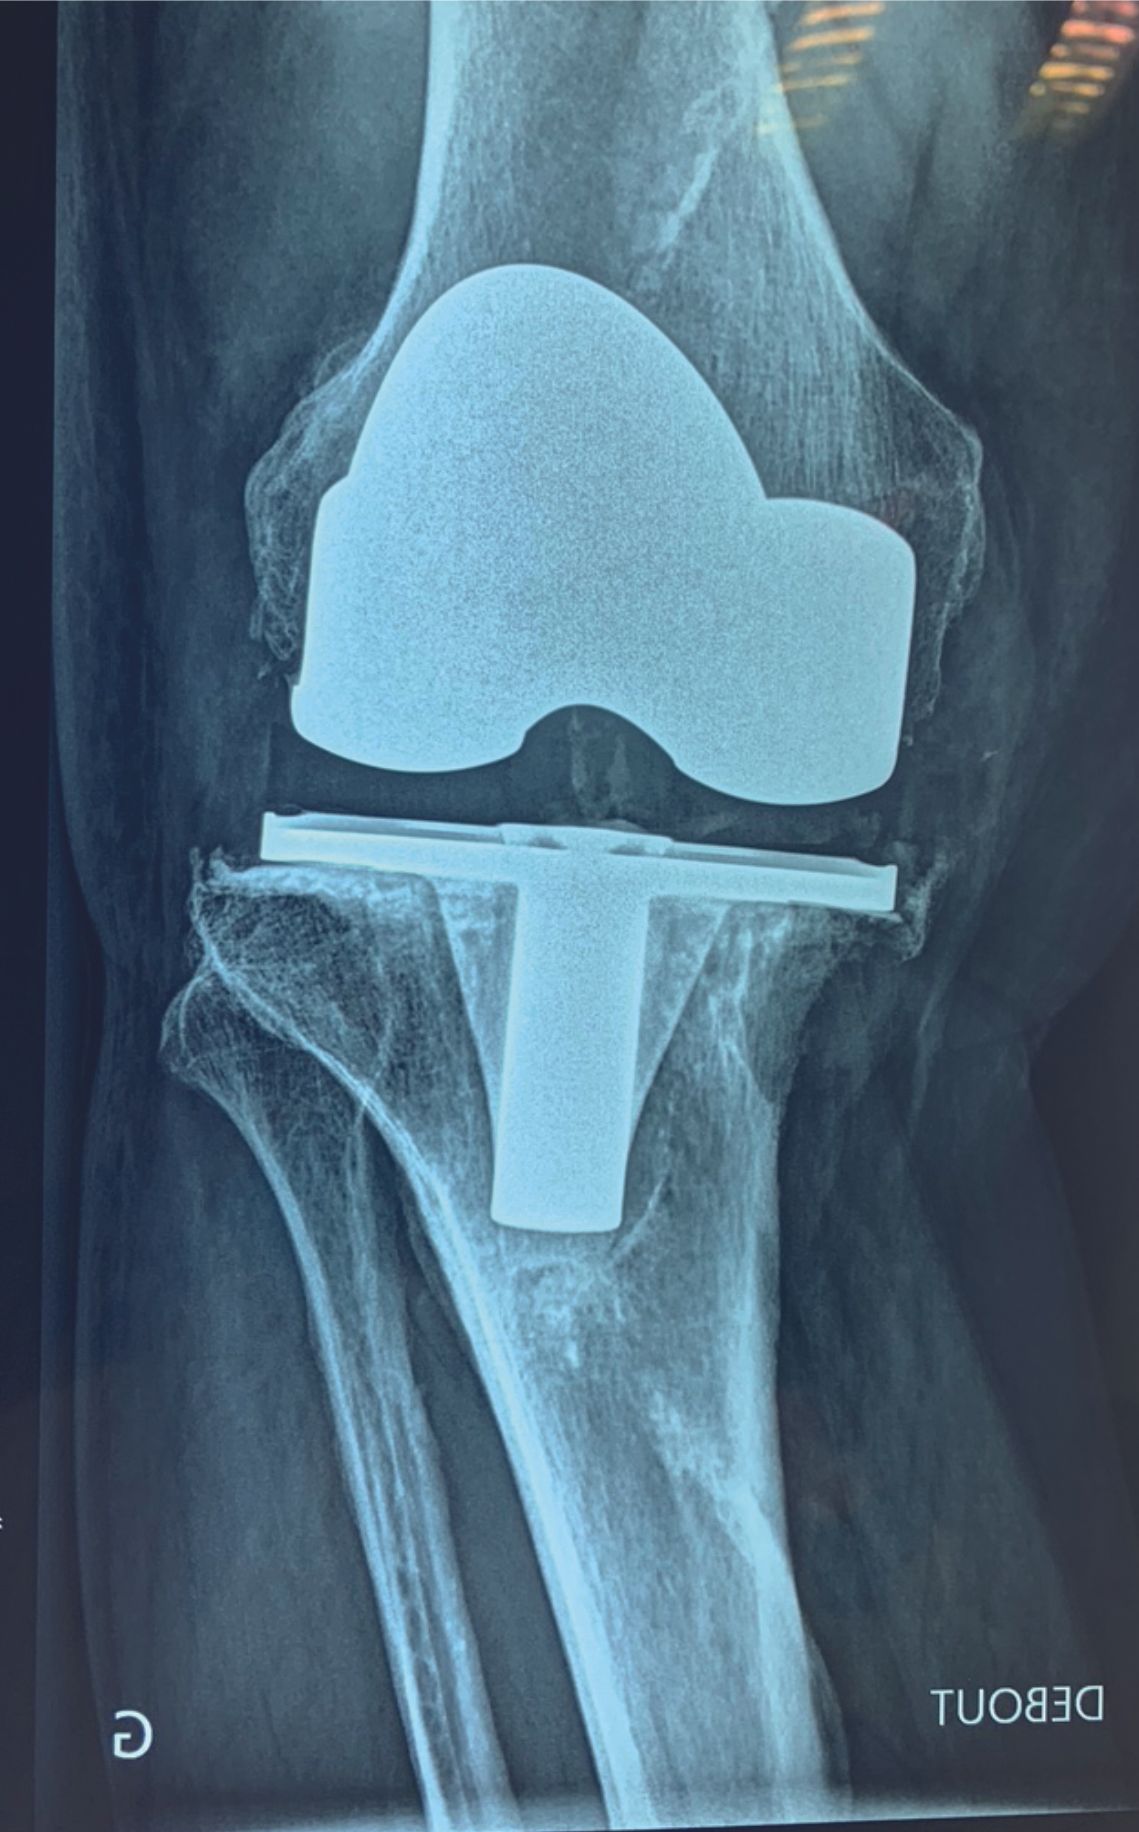

Mise au point Quel résultat attendre du traitement de l’instabilité prothétique du genou ? , Franck Remy Clinique de Saint-Omer, 71 Rue Ambroise Paré, 62575 Blendecques, France , Patrice Mertl CHU Amiens, Hôpital Nord, Place Victor Pauchet, 80052 Amiens, France 🖂 mertl.patrice@chu-amiens.fr N°341 - Février 2025 ● 12 min de lecture

Mise au point Les facteurs de raideur après PTG , Franck Remy Clinique de Saint-Omer, 71 Rue Ambroise Paré, 62575 Blendecques, France N°312 - Mars 2022 ● 11 min de lecture